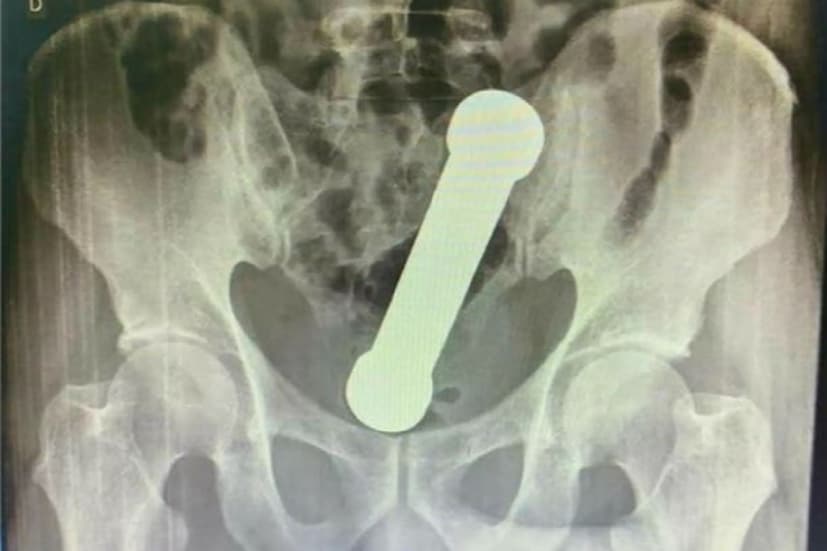

ইন্টারন্যাশানাল জার্নাল অফ সার্জারি কেস রিপোর্টে প্রকাশিত খবরে এই বিষয়টি সামনে এসেছে৷ ব্রাজিলের মুআউসের বাসিন্দা এক ব্যক্তির পেট ব্যাথা হয়৷ তারপর তাঁকে হাসপাতালে পাঠানো হয়৷ যেখানে চিকিৎসকরা তাঁর এক্সরে করানোর সিদ্ধান্ত নেন৷ সেখানে সেই বক্তি প্রচপর নাটক করে৷ ওই ব্যক্তি এক্সরে করানোর জন্য প্রস্তুত ছিল না৷ যদিও চিকিৎসকরা রিপোর্ট দেখে অবাক হয়ে যায়৷ ওই ব্যক্তির মলাশয়ে ২ কিলোর ডাম্বেল ঢুকেছিল৷

আন্তর্জাতিক জার্নাল অফ সার্জারি কেস রিপোর্টস অনুযায়ি এনা এলিসা ডি লন্ডা এয়র তাঁর দল বলেন প্রথমে তাঁরা ভেবেছিলেন টুইজার্সের সাহায্যে তা বার করে নেওয়া হবে৷ কিন্তু ডাম্বেল এতটাই ভারি ছিল যে তা এভাবে বার করা যায়নি৷ এরপর তাঁরা খুব ভয়ানক ভাবে ওই ডাম্বেলটা বার করে আনেন৷ ডাক্তাররা মলাশয়ে নিজের হাত ঢুকিয়ে মলাশয় থেকে বার করে আনেন৷